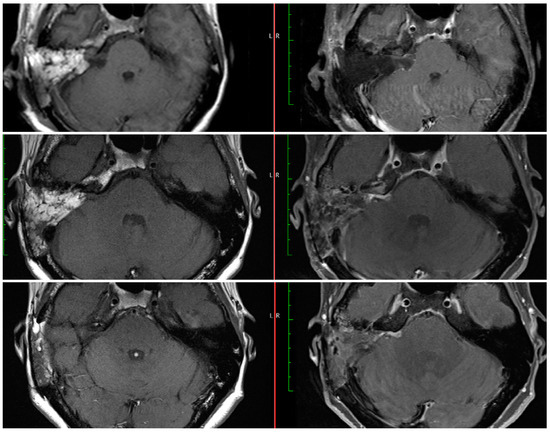

3.1.3. Follow-Up MRI Evaluation of EOR

All patients had follow-up imaging. Follow-up post-operative MRI (ranging 3 to 22 months) was available for eighteen patients with residual tumors (sixteen NTRs and two STRs). Lack of a residual tumor was confirmed via follow-up MRIs obtained around 3 and/or 12 months post-operatively on all patients in whom the intra-operative assessment was consistent with gross-total resection. As seen in Table 2, the resection assessment changed in six cases in between the immediate and delayed MRIs. In two cases, while a residual was seen on the immediate MRI, the delayed MRI was assessed as radiographic GTR. In two cases, while no residuals were seen on the immediate MRI, the delayed MRIs revealed residual tumors (both radiographic NTR; Figure 2). In the other two cases the assessment changed from radiographic STR to NTR.

Figure 2. Post-operative MRIs at day 1 (top), 3 months (middle), and 15 months (bottom) after NTR of a right sided vestibular schwannoma. The intra-operative residual estimate was 1 mm. The immediate MRI was a radiographic GTR, but the delayed MRIs were radiographic NTR with stable appearance of the area of enhancement.

While the timing and interval of the first post-operative MRI varies between surgeons and institutions, an early MRI during the post-operative inpatient stay could provide additional information to the surgeon. This immediate MRI is obtained on day one after the surgery at our institution. On the MRIs obtained months after the surgery, it may be difficult to differentiate scar tissue from a growing residual tumor [11,14]. An MRI obtained on post-operative day one does not include these nonspecific enhancements. The patient in Figure 2 (#6 in Table 2) had an extremely small residual about 1 mm and the immediate MRI confirmed the lack of a large residual tumor. While the later MRIs showed a larger area of enhancement than anticipated, comparison with the immediate post-operative MRI resulted in more confidence in the degree of resection and differentiation from later non-specific enhancements due to dural inflammation and/or connective tissue formation. As seen in Figure 2, the noted area of enhancement did not change in size from 3 to 15 months post-operatively. Although some studies have shown that these nonspecific enhancements can disappear with time, they may persist in other cases and continue to enhance after 5 years or longer [15,16]. This persistent enhancement can in turn result in a need for prolonged MRI surveillance. The recent survey of the ANS members revealed that a higher percentage of surgeons would follow linear enhancements for longer than 5 years and 14.3% would never stop ordering surveillance MRIs [13]. In this context, an early post-operative MRI could allow surgeons to evaluate the degree of resection and the presence of a residual tumor more accurately, and prior to any scar tissue formation. We believe that most of the changes between POD#1 and three months are attributable to enhancement seen with scarring. Hence, we anticipate that the three-month MRI may actually overestimate the extent of the residual tumor. In addition, the thickness of the obtained images can potentially result in missing small or thin residuals and a radiographic GTR should not obviate the need for continued surveillance in cases with a known residual. Furthermore, the current study was limited by its sample size and future studies will need to follow a larger cohort and compare the long-term appearances of residual tumors to those in the immediate post-operative MRIs.